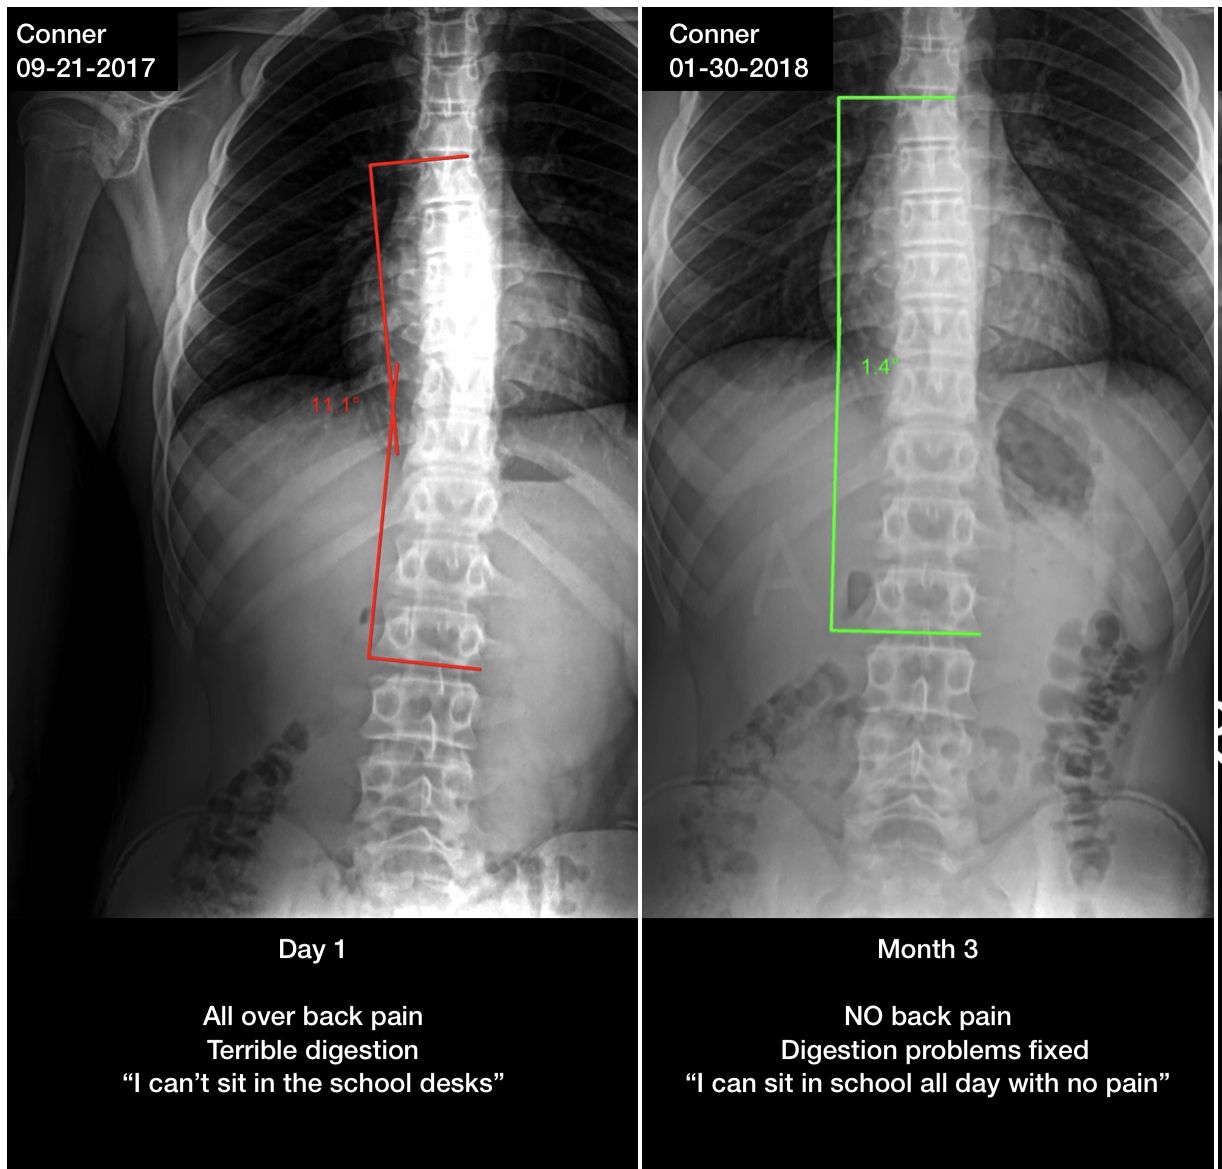

Curvature reduced from 11.1° to 1.4° in 3 months. Back pain and digestion issues resolved. "I can sit in school all day with no pain."